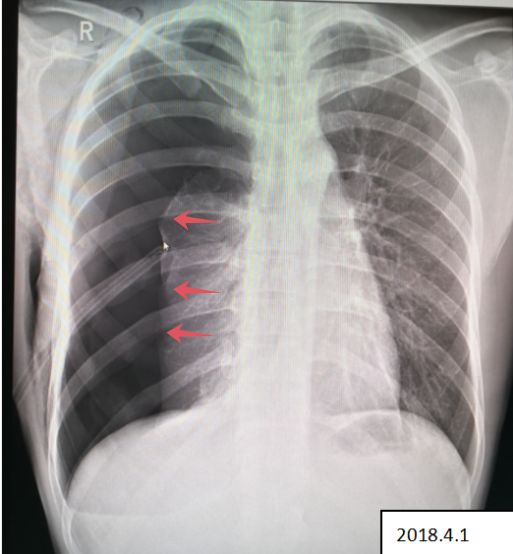

病例6

杨某,男,25岁,参加篮球比赛突发胸痛、呼吸困难,送医院检查。

病例6患者的X线胸片

患者右侧肺野内见带状异常透亮无肺纹理区,内侧缘可见发线状被压缩肺组织外缘(红色箭头),被压缩约75%以上,两肺门影不大,肋膈角清晰、锐利,心影形态、大小正常,纵隔稍向左移位。

2018.4.1 患者复查X线图像

患者右肺气胸复查所见:右侧肺野外带(约占肺野4/5)见带状异常透亮无肺纹理区,内侧缘可见发线状被压缩肺组织外缘,被压缩约75%以上,内可见引流管置入影。 右侧胸壁可见气体影。